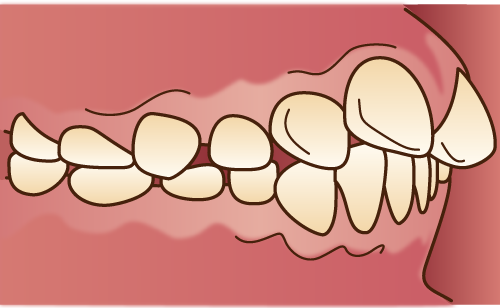

反対咬合(下顎前突)

下顎前突

下顎前歯が上顎前歯よりも、歯性、機能的、骨格的に前突し、正常咬合と逆になっている状態。

①上顎前歯が舌側傾斜もしくは転位している。

②臼歯部のう蝕による歯冠崩壊が著しい。

③下顎全体が近心転位している。

④上顎の発育不全がある。

①乳歯の萌出位置異常が原因になることがある。②臼歯部で咬めないなど、機能的に顎を前に出して前歯部で咬む癖がある人に多い。③遺伝的な場合がある。 ④口唇口蓋裂の人に多い。